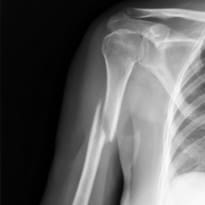

ऊपरी बांह की हड्डी को हुमेरुस कहा जाता है। यह वो हड्डी होती है जो कंधे से लेकर कोहनी तक जाती है। हुमेरुस के फ्रैक्चर यानी टूटने को दो तरह से विभाजित किया गया है: प्रोक्सिमल हुमेरुस फ्रैक्चर या हुमेरुस शाफ़्ट फ्रैक्चर। प्रोक्सिमल हुमेरुस फ्रैक्चर आमतौर पर कंधे के जोड़ के करीब होता है और विभिन्न फ्रैक्चर पैटर्न के साथ अलग-अलग स्तरों पर स्थित हो सकता है: सरल या विखण्डित। दूसरी ओर ह्यूमरस शाफ्ट फ्रैक्चर, वह है जो ऊपरी बांह के मध्य भाग में स्थानबद्ध होता है। बाजू का टूटना एक आम चोट है और यह आमतौर पर कार दुर्घटना या किसी अन्य प्रकार की दुर्घटना के कारण गिरने का परिणाम है।

- आपके डॉक्टर आपकी बाजू की जांच कर के हुमेरुस फ्रैक्चर का निदान करेंगे। आपको X-Ray की सलाह भी दे सकते हैं। हुमेरुस फ्रैक्चर का उपचार कई चीज़ों पर निर्भर करता हैं जैसे फ्रैक्चर का प्रकार कौन सा है और क्या इससे हड्डी के टुकड़े हुए हैं? डॉक्टर आपकी बाजु से कुछ मूवमेंट भी करा सकते हैं ताकि इसका पता चल सके कि फ्रैक्चर किस प्रकार का है और क्या आपको कोई और चोट तो नहीं लगी है।